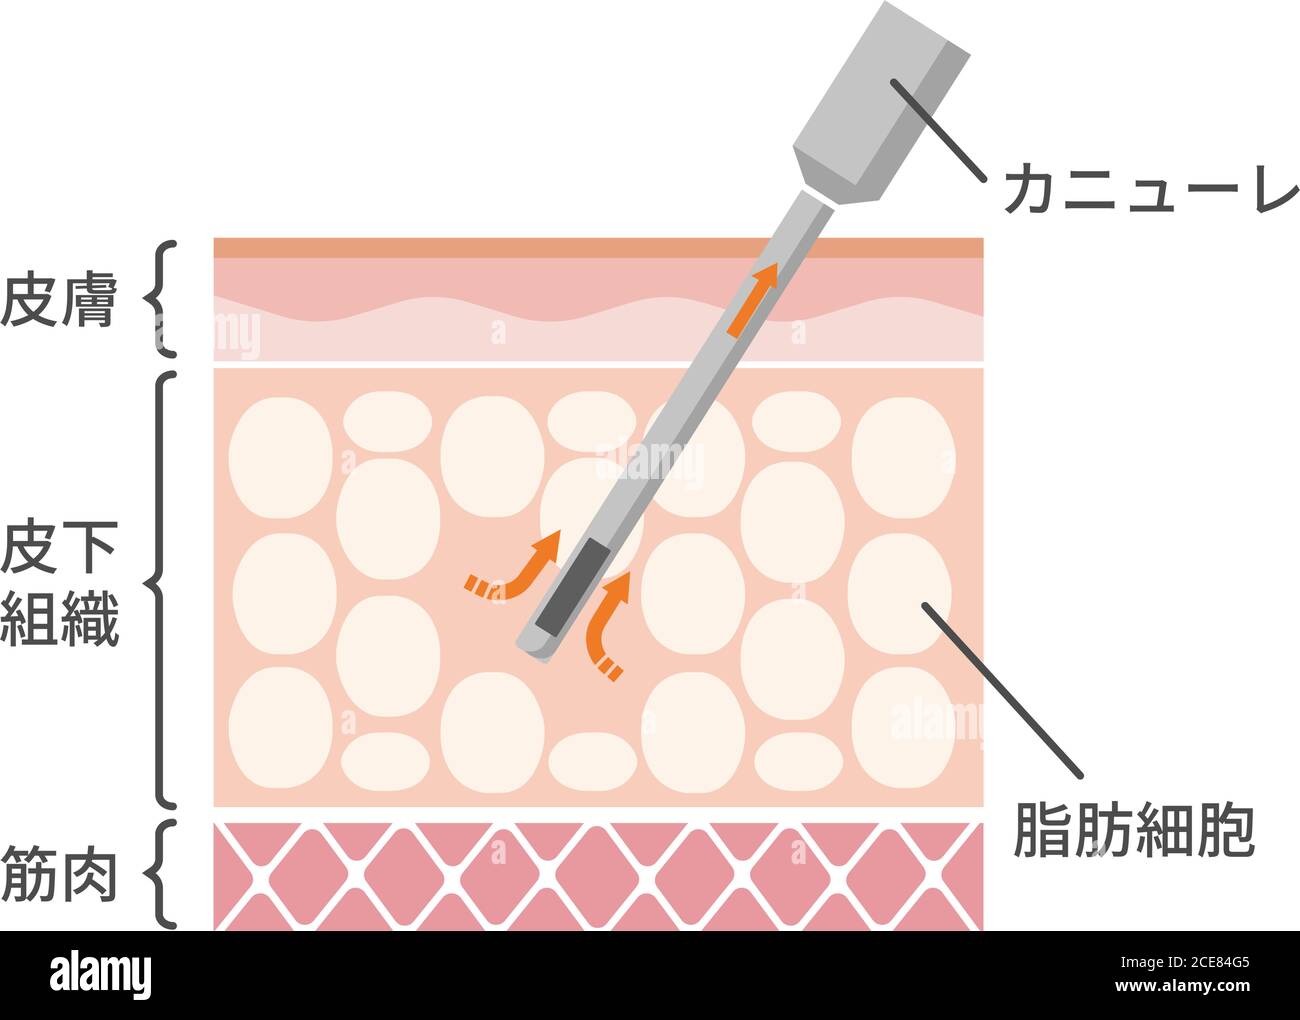

Illustration vectorielle du processus de liposuccion / vue en coupe de la peau Illustration de Vecteurhttps://www.alamyimages.fr/image-license-details/?v=1https://www.alamyimages.fr/illustration-vectorielle-du-processus-de-liposuccion-vue-en-coupe-de-la-peau-image370202117.html

Illustration vectorielle du processus de liposuccion / vue en coupe de la peau Illustration de Vecteurhttps://www.alamyimages.fr/image-license-details/?v=1https://www.alamyimages.fr/illustration-vectorielle-du-processus-de-liposuccion-vue-en-coupe-de-la-peau-image370202117.htmlRF2CE84G5–Illustration vectorielle du processus de liposuccion / vue en coupe de la peau